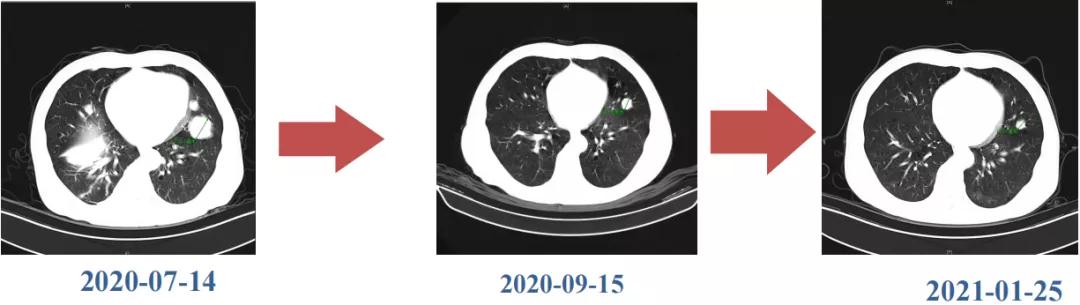

Δ肺CT:双肺多发转移

肿瘤学评估(用药后2个月对比6个月):肝内主瘤明显缩小,动脉期强化降低;子灶消失;门脉右支癌栓明显缩小坏死;肺转移灶缩小,大部分消失。

Δ治疗过程中病灶影像学变化

用药6个月后:肝脏病灶明显缩小,子灶消失,仅有少量动脉期强化;肺转移单个持续缩小稳定,PET CT活性弱;HBV DNA 转阴;可考虑转化切除。